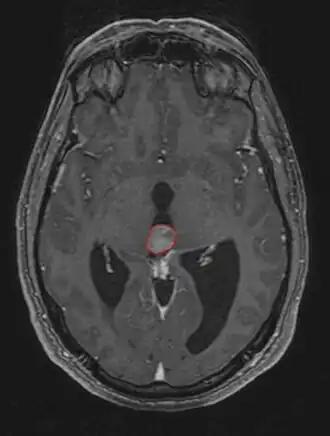

Пинеалома — опухоль головного мозга, исходящая из шишковидного тела. Это гетерогенная группа новообразований, локализующихся в пинеальной области (задние отделы III желудочка, область цистерны четверохолмия) и имеющих различное происхождение. Развитие пинеаломы может быть связано с опухолевой трансформацией пинеалоцитов, астроцитов или гоноцитов[2][3]. Опухоль, развившаяся из пинеалоцитов, в зависимости от степени дифференцировки носит название пинеоцитома, пинеальная паренхиматозная опухоль промежуточной дифференцировки, пинеобластома. Опухоли астроцитарного происхождения имеют типичное строение. Наиболее характерным для астроцитомы является медленный, инфильтративный рост.

Симптомы опухоли обусловлены её расположением. Наиболее частыми симптомами являются головные боли, тошнота и рвота. Они обусловлены повышением внутричерепного давления вызванного обструктивной гидроцефалией, которая возникает при сдавлении опухолевой массой водопровода мозга и нарушением циркуляции спинномозговой жидкости.

Компрессия верхнего двухолмия опухолью приводит к синдрому Парино - невозможности вертикальных движений глаз, небольшой дилатации зрачка. Возможно развитие отёка соска зрительного нерва